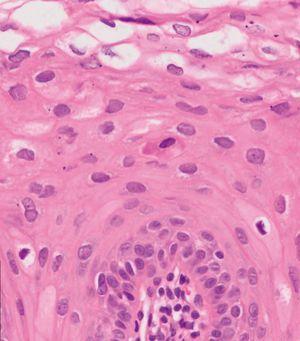

En el estudio histológico se observaba una hiperplasia epidérmica, acantosis, paraqueratosis leve, proyecciones papilares con zonas de anastomosis horizontal (fig. 3). Aparecían coilocitos y células disqueratósicas o apoptóticas que simulan la mitosis (fig. 4) en las capas superficiales de la epidermis.

Figura 4. Coilocitos y células mitosis-like en epidermis. Hematoxilina-eosina, ×400.